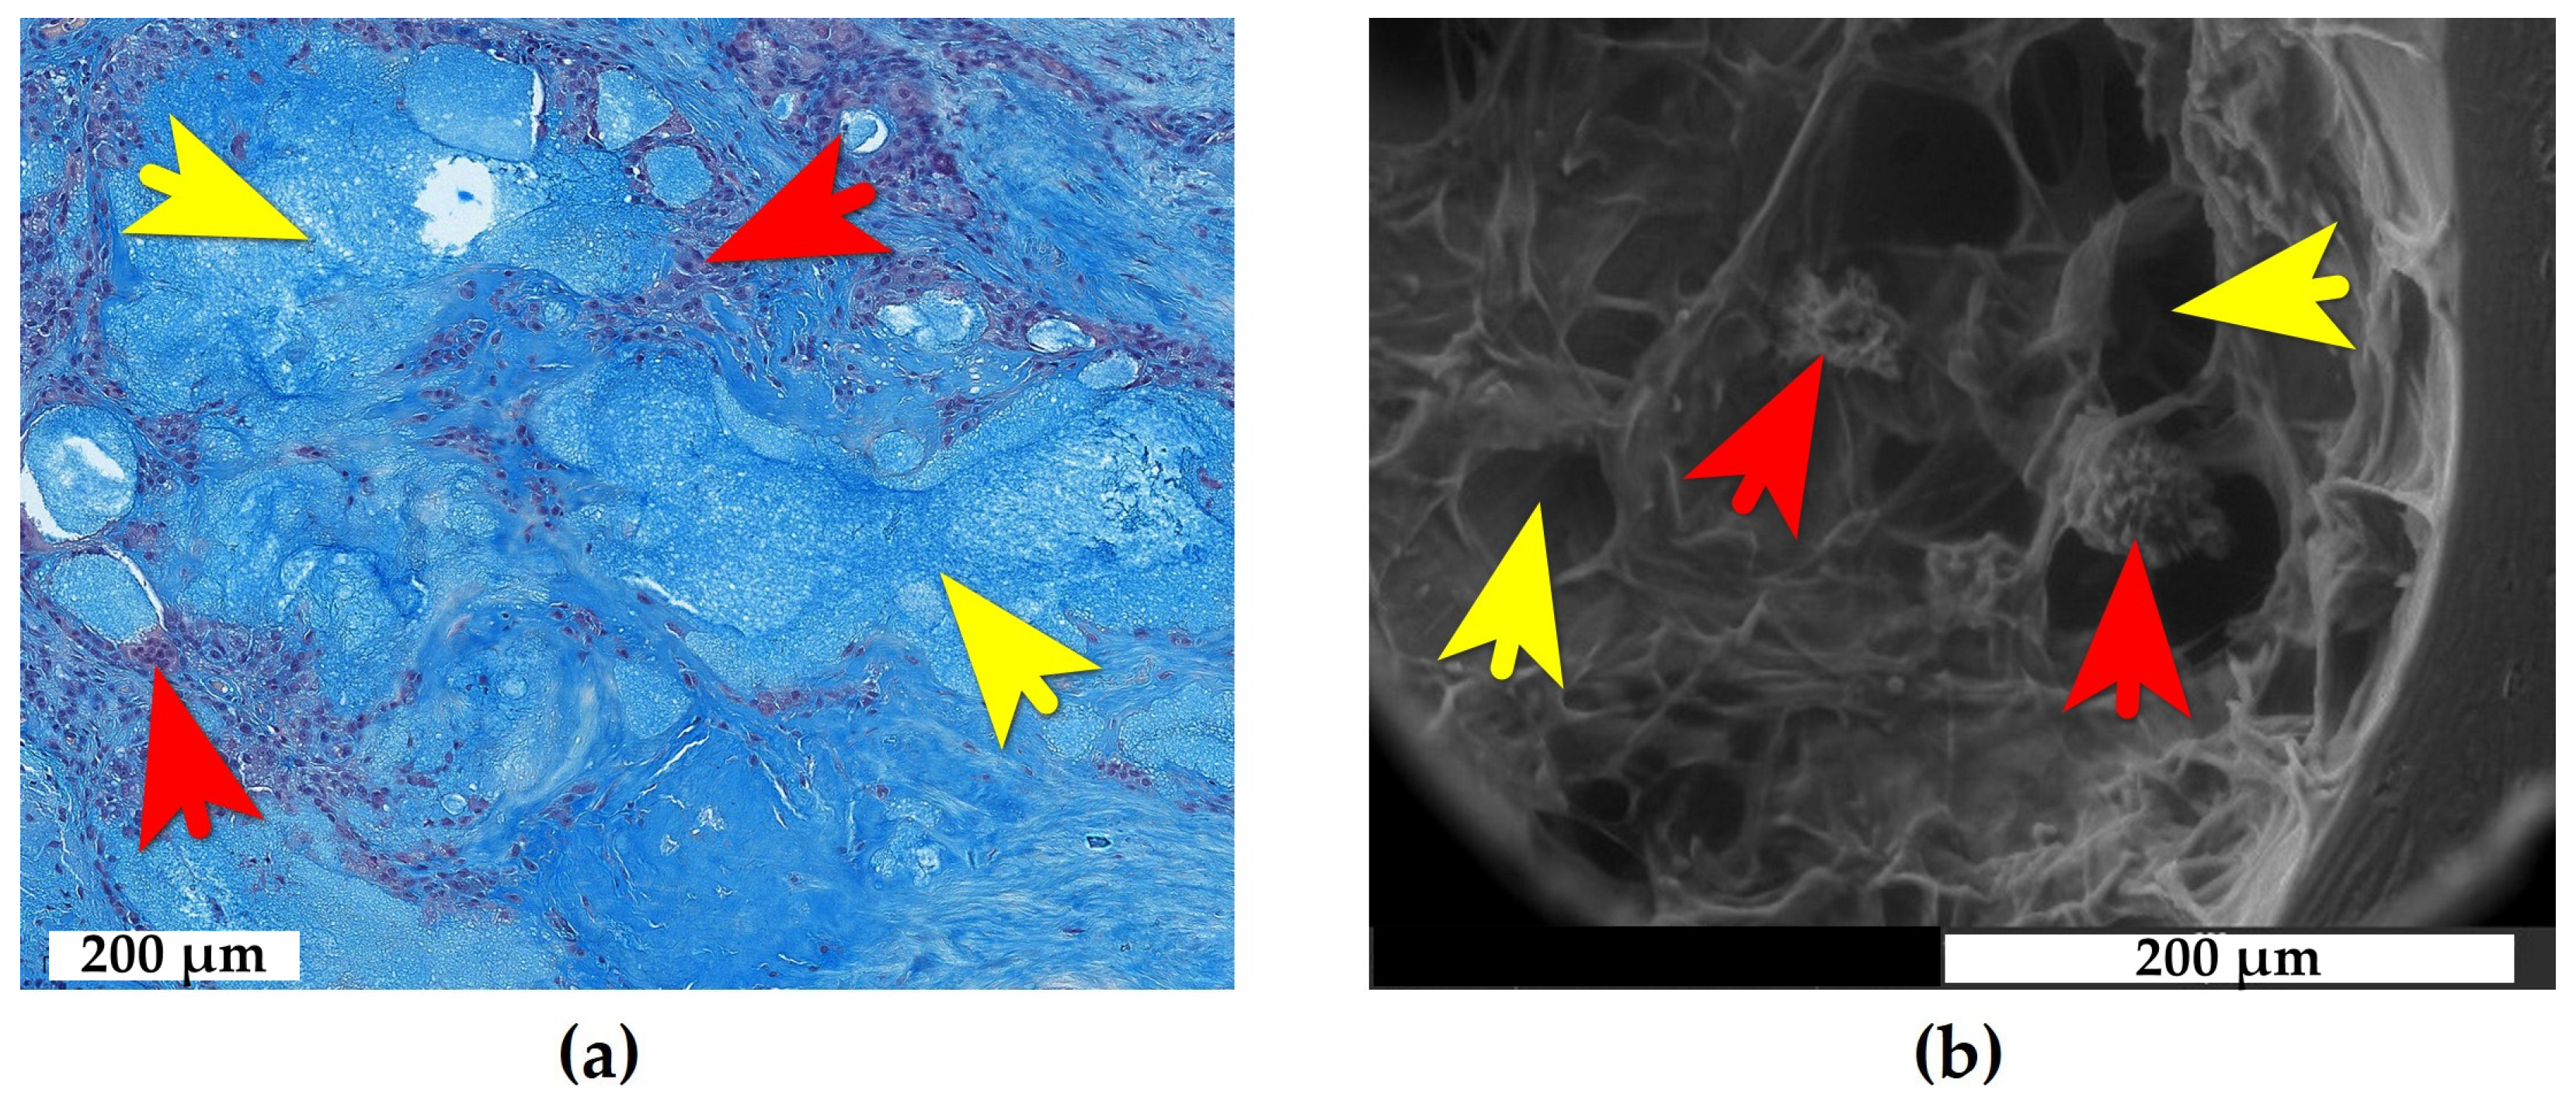

2.1. Adipose Tissue Response to e-HA

2.2. Synovial Tissue Response to e-HA

2.3. Bone Tissue Response to e-HA